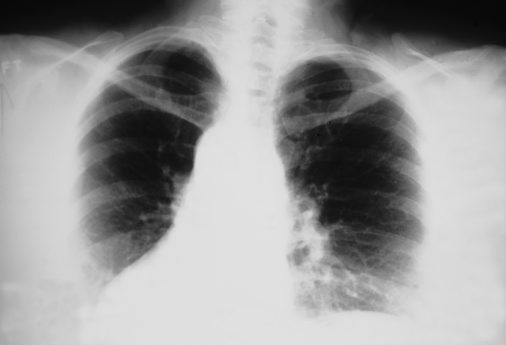

Ученые из Томска создали метод предоперационной диагностики распространения рака легкого, который позволит уменьшить смертность и улучшить качество жизни пациентов. Об этом сообщил ТАСС со ссылкой на пресс-службу Сибирского государственного медуниверситета (СибГМУ). «Ученые Сибирского медуниверситета и НИИ онкологии Томского НИМЦ провели ретроспективное исследование группы больных с немелкоклеточным раком легкого», – заявил вуз. По информации учебного заведения, специалисты обнаружили клинико-морфологические параметры, которые связаны с распространением опухоли по воздуху. Эксперты, основываясь на гистологическом и иммуногистохимическом исследованиях биопсийного материала, разработали технологию прогнозирования. Метод предложили внедрить в работу онкологических учреждений. На изобретение получили патент.